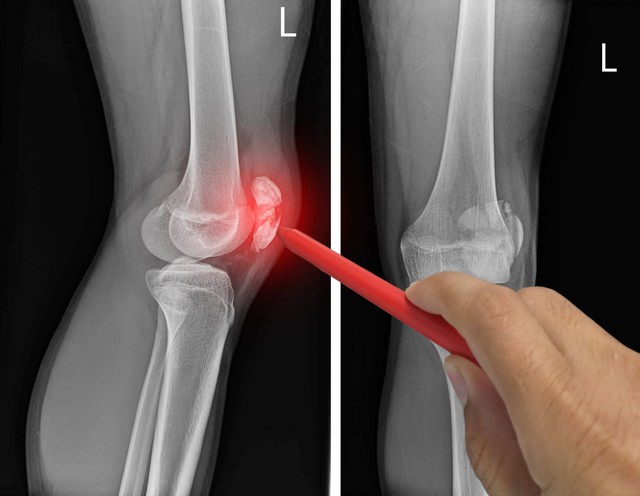

Porckopás okozta térdfájdalom: így vethet véget a fájdalomnak

Az évek előrehaladtával szinte nincs is olyan ember, akinél ne jelentkeznének különböző reumatológiai fájdalmak, a térdfájdalom is közéjük tartozik. Mi állhat a hátterében, és hogyan lehet védekezni ellene?

Porckopás a térdben: ezzel a kezeléssel jobb, ha vigyáz!

Képalkotó alapján nem szabad diagnosztizálni. Először meg kell keresni a probléma okát, hiszen térdfájdalmat a testünk igen különböző pontjai is tudnak okozni.